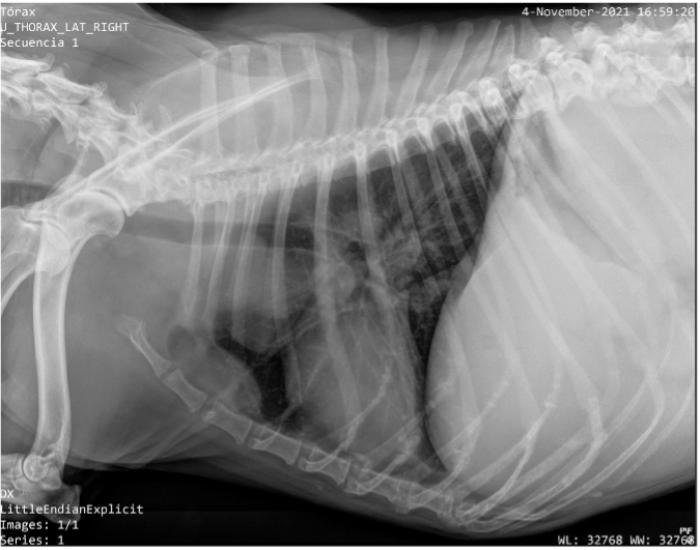

Una emergencia por un derrame es indudablemente más frecuente cuando afecta al saco pericárdico. Los tumores cardíacos más frecuentes son los hemangiosarcomas (HSC) cardíacos y las neoplasias neuroendocrinas del cuerpo aórtico (NCA). En el caso del HSC los derrames suelen ser hemorrágicos y en los NCA serosanguinolentos. El espacio pericárdico es el que menos cantidad de líquido puede alojar, por lo cual las colectas pueden llevar a un aumento de presión dentro del saco que puede colapsar el corazón derecho llevando a una emergencia. El paciente puede tener al examen general sonidos cardíacos apagados, pulso débil, signo hepatoyugular, debilidad, congestión hepática y llevarlo directamente a un estado de shock. Los hallazgos en las radiografías simples pueden hacer sospechar de una colecta pericárdica debido al hallazgo típico de una silueta cardíaca de aspecto globoso y la ultrasonografía confirma la sospecha (Figura 3).

Con la ultrasonografía se puede evidenciar la colecta pericárdica con facilidad e incluso puede ser usada para guiar el drenaje. El líquido pericárdico obtenido debe acondicionarse con y sin anticoagulante, centrifugar y analizar el sedimento para realizar citología. Es importante recordar que, si bien está indicado el análisis del líquido, lamentablemente pocas veces alcanza un nivel de confianza tal que permita validar un diagnóstico definitivo; la concentración mediante cytospin o citocentrífuga permite aumentar la sensibilidad de la muestra.